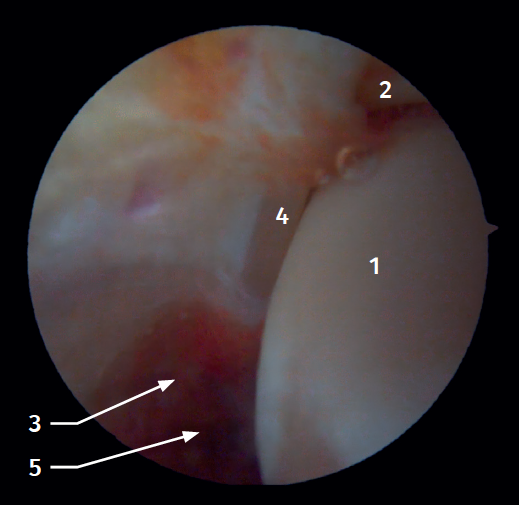

El 20% del LTPA es intraarticular(7). Cuando realizamos un acceso anteromedial del tobillo dirigiendo el artroscopio hacia lateral podemos ver las fibras distales del LTPA con su disposición oblicua y su continuación con el ligamento peroneo-astragalino anterior (Figura 2). Si avanzamos dentro de la articulación tibioastragalina, veremos la articulación tibioperonea distal con el receso sindesmal ocupado de tejido sinovial (Figura 3).

Figura 2. Visión artroscópica anterolateral del tobillo derecho. 1: cúpula astragalina; 2: cara anterior de la tibia; 3: peroné; 4: fibras distales del ligamento tibioperoneo anterior; 5: ligamento peroneo-astragalino anterior.

Figura 3. Visión artroscópica anterolateral de un tobillo derecho al introducirnos en la tibioastragalina. 1: cúpula astragalina; 2: cara articular de la tibia; 3: peroné; 4: articulación tibioperonea distal; 5: fibras distales del ligamento tibioperoneo anterior.